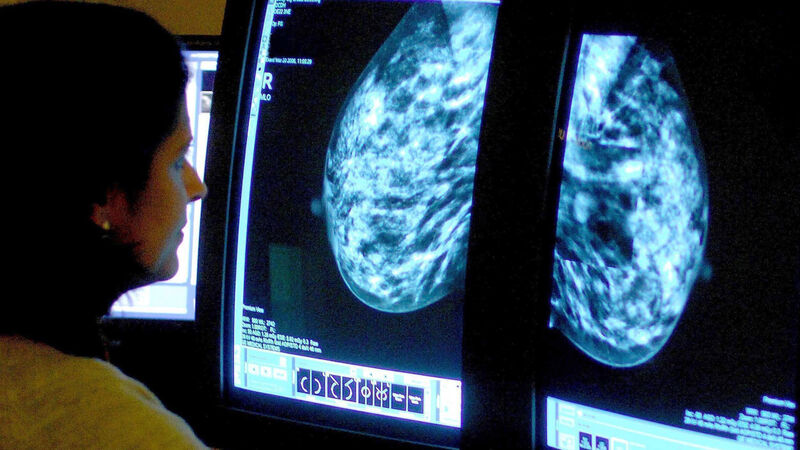

Signs of heart disease can be picked up in breast cancer screenings through the use of artificial intelligence (AI), researchers have found.

Experts used AI to look for calcification in breast arteries, a substance that increases the risk of heart attack, stroke and early death.

Adding AI to breast cancer screenings in this way could help find thousands of women with undiagnosed heart disease, according to the largest study of its kind.

"Mammograms, which women already attend for breast cancer screening, can also reveal calcium deposits in breast arteries and this is linked to heart disease.

AI was used to look for calcium deposits in the arteries of breast tissue, which is known to harden arteries and can increase the risk of heart attack and stroke.